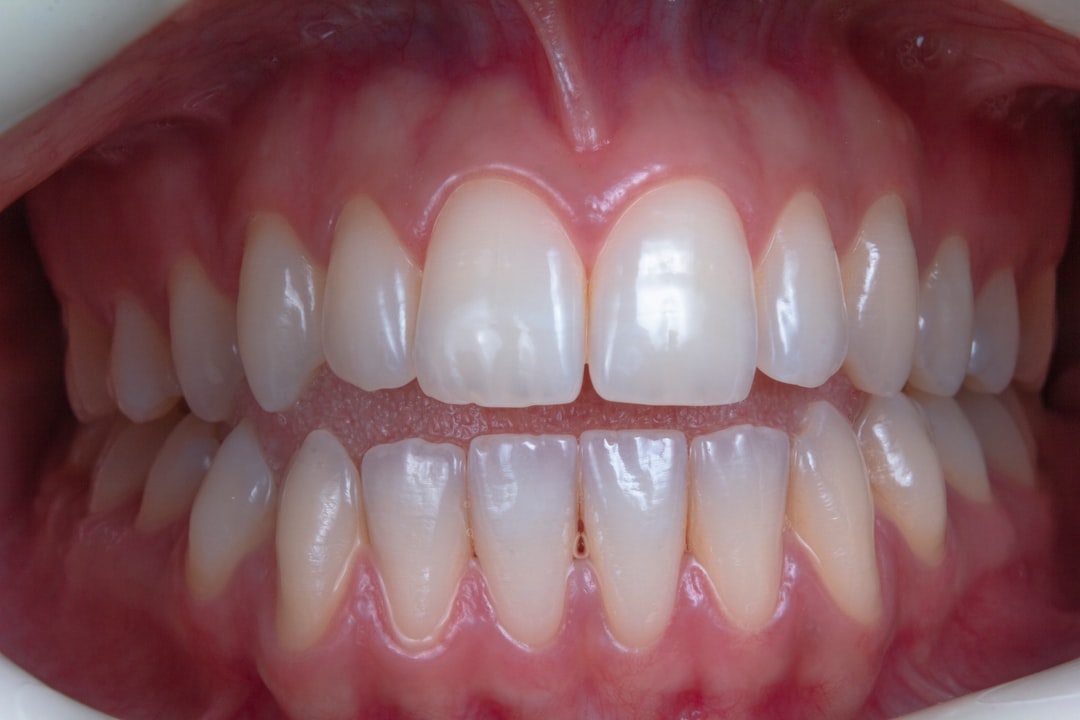

우리의 치아 개수는 구강 건강의 기본을 형성합니다. 일반적으로 성인의 경우 성인 치아 개수는 32개입니다. 이 개수는 모두 건강해야 하며 기능을 제대로 수행해야 우리의 식사, 말하기, 그리고 자신감을 지켜줄 수 있습니다. 치아 개수가 부족하거나 손상되면 여러 문제들이 발생할 수 있습니다. 따라서, 치아 개수를 정기적으로 확인하고 관리하는 것은 매우 중요합니다. 구강 건강은 종종 우리가 예기치 않게 간과하는 부분이며, 그 중요성을 많은 사람들이 알지 못합니다.

성인이 되면 성인 치아 개수는 평균 32개로 나타납니다. 상악과 하악 각각 16개가 나누어진 형태이며, 대개 4개의 사랑니가 포함됩니다. 하지만 모든 성인이 그렇듯, 어떤 사람들은 사랑니의 발달로 인해 다소 차이가 발생할 수 있습니다. 더군다나, 성년기에 접어든 시점에서 잃어버린 치아가 있다면, 남아있는 개수가 줄어드는 것이 자연스러운 현상입니다. 하지만 이는 피할 수 있는 문제이므로, 치아 개수 관리는 필요합니다.